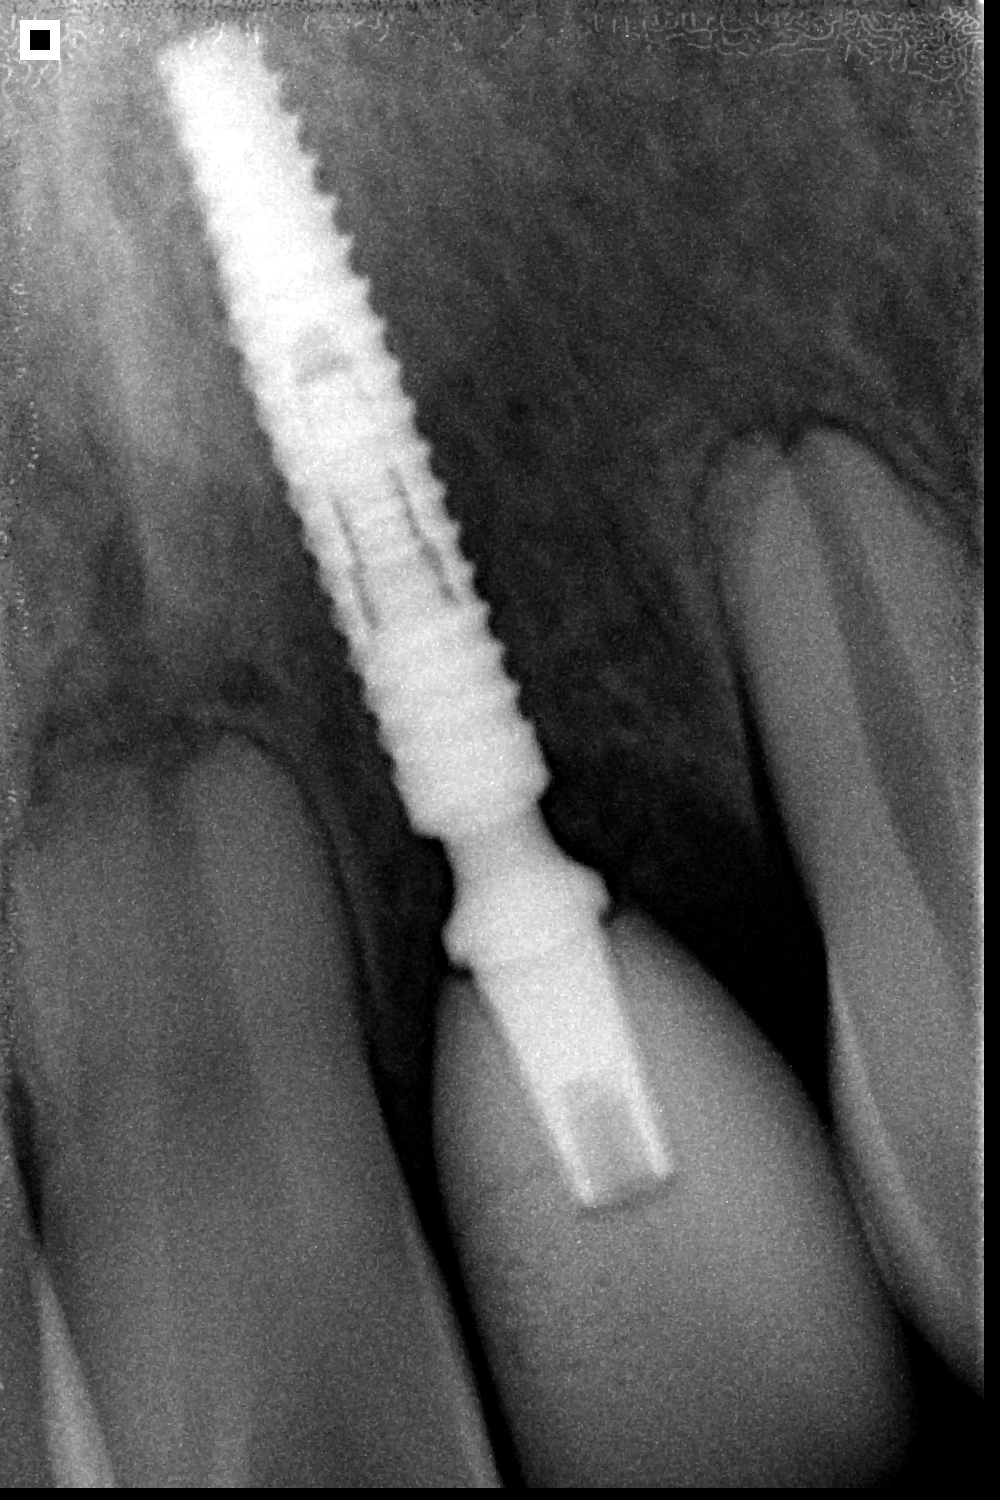

UNITITE SLIM

Con apenas 2.9 mm de diámetro, Unitite Slim proporciona rehabilitaciones en áreas estrechas y espacios interdentales limitados, como las regiones de los incisivos laterales superiores y de los incisivos inferiores.

Ofrece tres longitudes diferentes para su planificación quirúrgica. Su dimensión reducida protege estructuras bucales y su vascularización

Sistema Cono Morse: Superioridad biomecánica de los acoplamientos protésicos con ángulo interno de 3 grados.

Fabricado en titanio grado 4 Cold Worked

Esta técnica de fabricación ofrece estabilidad y resistencia mecánica a longo plazo para

implantes con paredes delgadas.